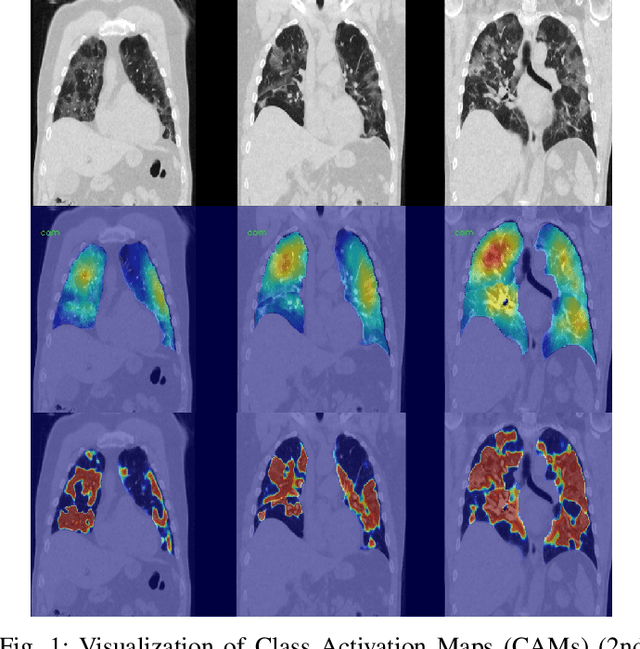

Automatic lesion segmentation on thoracic CT enables rapid quantitative analysis of lung involvement in COVID- 19 infections. Obtaining voxel-level annotations for training segmentation networks is prohibitively expensive. Therefore we propose a weakly-supervised segmentation method based on dense regression activation maps (dRAM). Most advanced weakly supervised segmentation approaches exploit class activation maps (CAMs) to localize objects generated from high-level semantic features at a coarse resolution. As a result, CAMs provide coarse outlines that do not align precisely with the object segmentations. Instead, we exploit dense features from a segmentation network to compute dense regression activation maps (dRAMs) for preserving local details. During training, dRAMs are pooled lobe-wise to regress the per-lobe lesion percentage. In such a way, the network achieves additional information regarding the lesion quantification in comparison with the classification approach. Furthermore, we refine dRAMs based on an attention module and dense conditional random field trained together with the main regression task. The refined dRAMs are served as the pseudo labels for training a final segmentation network. When evaluated on 69 CT scans, our method substantially improves the intersection over union from 0.335 in the CAM-based weakly supervised segmentation method to 0.495.